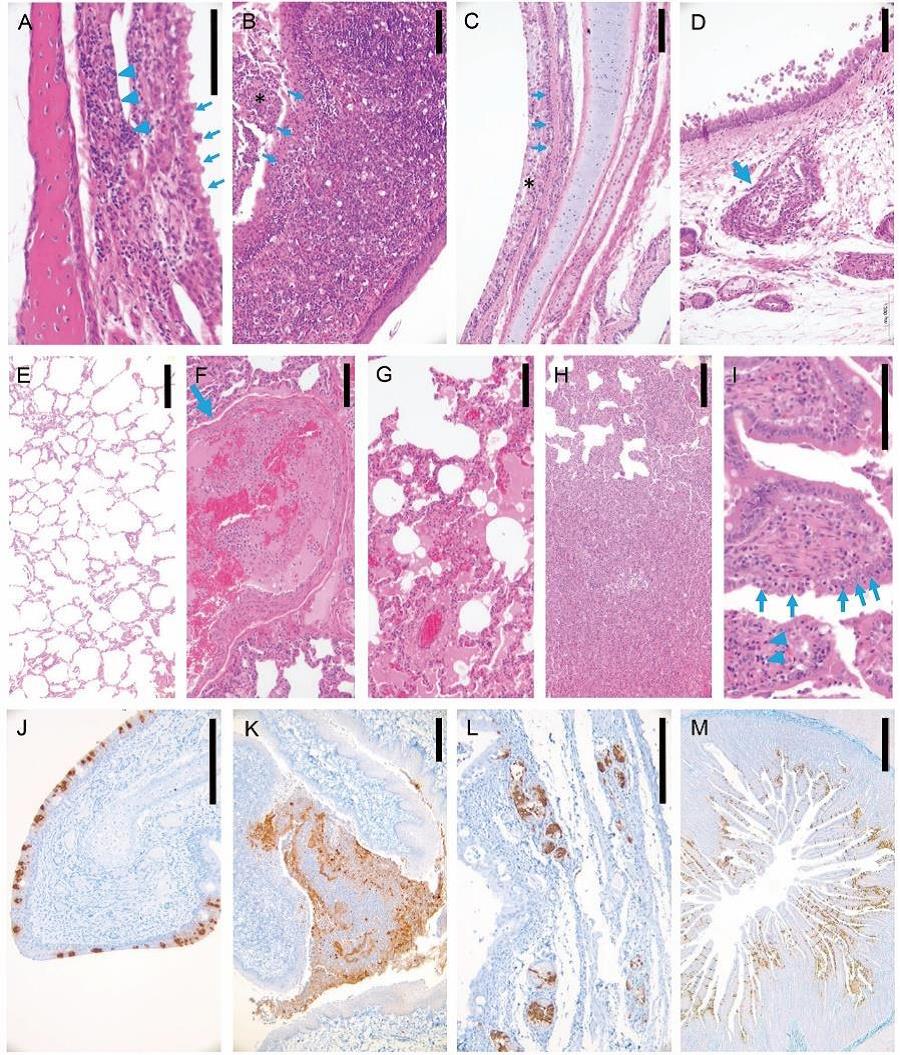

圖. SARS-CoV-2在感染貓呼吸系統(tǒng)及消化系統(tǒng)高效復(fù)制,引起病理?yè)p傷和炎癥反應(yīng)

病毒感染后3天病死或安樂(lè)死貓組織病理學(xué)及免疫組化研究。(A)鼻粘膜上皮排列紊亂,纖毛脫落 (箭頭), 固有層淋巴細(xì)胞侵潤(rùn)(箭頭)。(B) 扁桃體上皮細(xì)胞變性、壞死,粘膜上皮(星號(hào))表面覆蓋細(xì)胞碎片及中性粒細(xì)胞(箭)。(C)氣管粘膜上皮變性、壞死(箭),表面覆蓋混有大量細(xì)胞碎片的黏液(星號(hào))。(D)氣管黏液腺上皮壞死,淋巴細(xì)胞侵潤(rùn)(箭)。(E)未感染病毒貓肺正常組織結(jié)構(gòu)。(F)肺血管內(nèi)炎癥細(xì)胞聚集,纖維蛋白凝結(jié)形成(箭)。(G)肺泡內(nèi)即肺泡間隔大量巨噬細(xì)胞及淋巴細(xì)胞侵潤(rùn)。(H)肺泡及肺泡間隔炎性侵潤(rùn)和增生。(I)小腸上皮部分細(xì)胞變性、壞死,固有層中等程度淋巴細(xì)胞侵潤(rùn)(箭)。 (J)鼻甲粘膜上皮細(xì)胞大量病毒抗原陽(yáng)性(棕色)。(K)扁桃體粘膜上皮及粘膜表面脫落細(xì)胞大量病毒抗原陽(yáng)性(棕色)。(L)氣管黏液腺漿液細(xì)胞大量病毒抗原陽(yáng)性(棕色)。(M)小腸粘膜上皮細(xì)胞大量病毒抗原陽(yáng)性(棕色)。標(biāo)尺線 A, I = 100 μm, B-H, J-L = 200 μm, M = 500 μm.